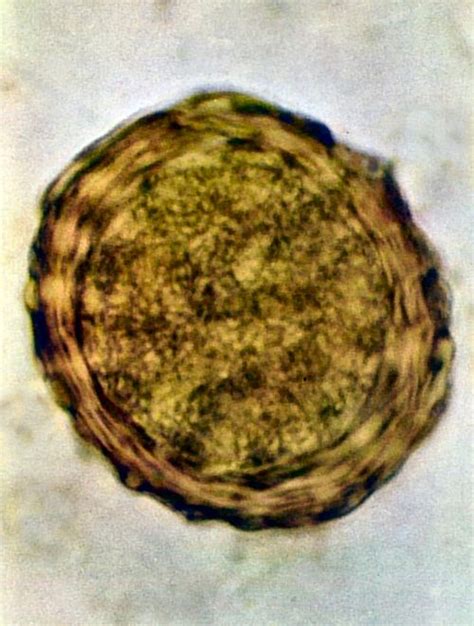

Plesňové alebo bakteriálne infekcie pokožky hlavy, ako je seboroická dermatitída, folikulitída alebo tinea capitis (mykóza pokožky hlavy), môžu viesť k zvýšenému zápachu. Tieto infekcie často sprevádzajú aj ďalšie príznaky ako svrbenie, začervenanie, olupovanie alebo tvorba vyrážok a pustúl.